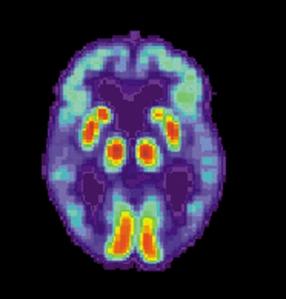

Colecciones de proteínas duras, enlazadas entre sí y llamadas placas, se encuentran entre las células nerviosas en casi todos los pacientes de Alzheimer, y son los responsables más probables de la pérdida de las funciones cerebrales y motoras asociadas a la enfermedad. Estas placas pueden ser inducidas en ratones sanos mediante una inyección de tejido cerebral afectado.

“La acumulación de proteínas inducidas ha disparado también varios cambios inflamatorios degenerativos comúnmente observados en los cerebros de los pacientes con la enfermedad de Alzheimer,” dijo Mathias Jucker, del Instituto Hertie of Clinical Brain Research, en Tübingen, Alemania, y autor del estudio publicado en Science.

En el estudio, los investigadores retiraron el tejido cerebral de ratones con síntomas similares a Alzheimer, que fue inyectado en la cavidad del estómago de ratones sanos. Cuatro meses más tarde, los ratones previamente sanos mostraron síntomas similares a los de la enfermedad de Alzheimer y sus cerebros habían creado tejido cerebral de manera similar la enfermedad.

El desarrollo de la enfermedad en ratones sanos demuestra que hay un mecanismo previamente desconocido por el cual el tejido infeccioso puede moverse por todo el cuerpo y pasar a través de las barreras que rodean el cerebro. No está claro, sin embargo, cómo el material inyectado causa la enfermedad.